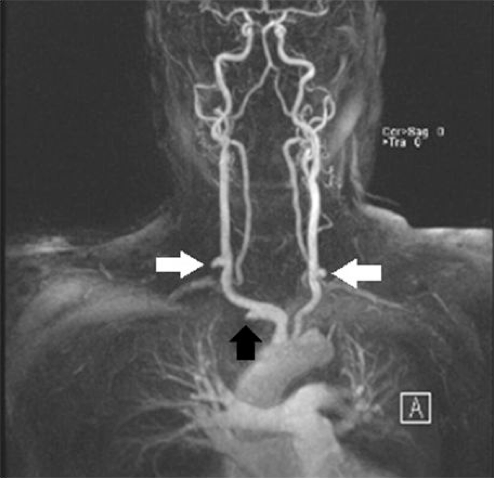

Figure 2. Computerized tomography angiogram taken upon admission to our facility. Bilateral SCA-CCA graft occlusion can be noted (white arrows), along with the surgically ligated right SCA (black arrow) (click thumbnail to view larger image).

Upon transfer to our facility, a computed tomography angiogram (CTA) was performed, which revealed the bilaterally occluded bypass grafts and the ligated right SCA (Figure 2). Cardiac catheterization and angiography showed that both the proximal RCA and the left main were occluded. The SVG to RCA and OM1 were patent; SVG to D1 was occluded. The bilateral subclavian steals could be visualized with contrast injection into the bracheocephalic and left common carotid arteries (Figures 3 and 4). The LIMA was faintly visualized during the late filling phase of the left carotid angiogram (Figure 4); the left SCA and LIMA filled via collaterals from the left vertebral artery.